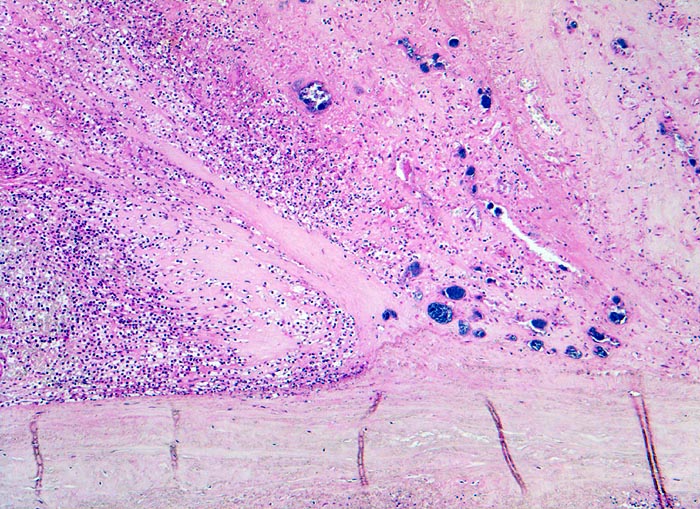

Endocarditis ulcero-polyposa der Aortenklappe

Dem fibrösen Klappengerüst aufgelagerte Klappenvegetation bestehend aus Fibrin, neutrophilen Granulozyten und herdförmig eingelagerten blauen Bakterienrasen.

Akut einsetzendes Krankheitsbild mit Fieber, Schüttelfrost, Müdigkeit und Dyspnoe. Blutkulturen wiederholt positiv für Staphylokokkus aureus. Keine Klappenvorschädigung bekannt.

Histologie

50